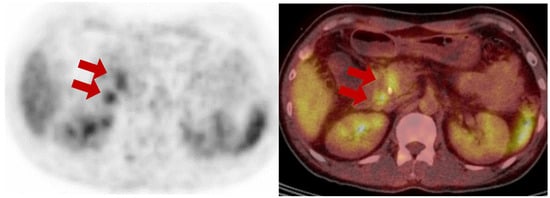

A 49-year-old male presented with abdominal discomfort and underwent computed tomography (CT) at a local clinic which revealed dilatation of the common bile duct (CBD) and intrahepatic ducts (IHD). The patient was referred to a specialized center for further evaluation to exclude CBD cancer. The laboratory results revealed a normal white blood cell count of 7550/µL, a typical hemoglobin level of 13.0 g/dL, and a platelet count within the expected range of 239 × 103/µL. Kidney function appeared normal, with a blood urea nitrogen (BUN) level of 11.6 mg/dl and a creatinine level of 0.7 mg/dL. However, there were significant abnormalities in liver function, including elevated levels of aspartate aminotransferase (AST) at 175 U/L, alanine aminotransferase (ALT) at 295 U/L, and alkaline phosphatase (428 U/L). The total bilirubin level was notably high at 11.54 mg/dL, with direct bilirubin level of 10.45 mg/dL. Furthermore, gamma-glutamyl transferase levels were substantially elevated (1255 U/L). In addition, an elevated C-reactive protein level (1.31 mg/dL) was also observed. His body mass index (BMI) was 23.9, and he had no history of diabetes, hypertension, or fatty liver disease. Endoscopic retrograde cholangiopancreatography (ERCP), biopsy, and endoscopic nasobiliary drainage (ENBD) insertion were performed to confirm the diagnosis. The pathological results of the CBD biopsy confirmed the presence of a moderately differentiated adenocarcinoma. To determine the stage of cancer, MRI of the liver and a 18F-FDG PET/CT scan were conducted. The 18F-FDG PET/CT scan showed focal uptake in the mid-CBD, where a biopsy was performed, indicating CBD cancer. The axial PET and fusion images from 18F-FDG PET/CT show focal uptake (red arrows) in the common bile duct with a drainage catheter and the posterior duodenopancreatic area, suggesting biopsy-proven primary cancer and a regional metastatic lymph node, respectively.